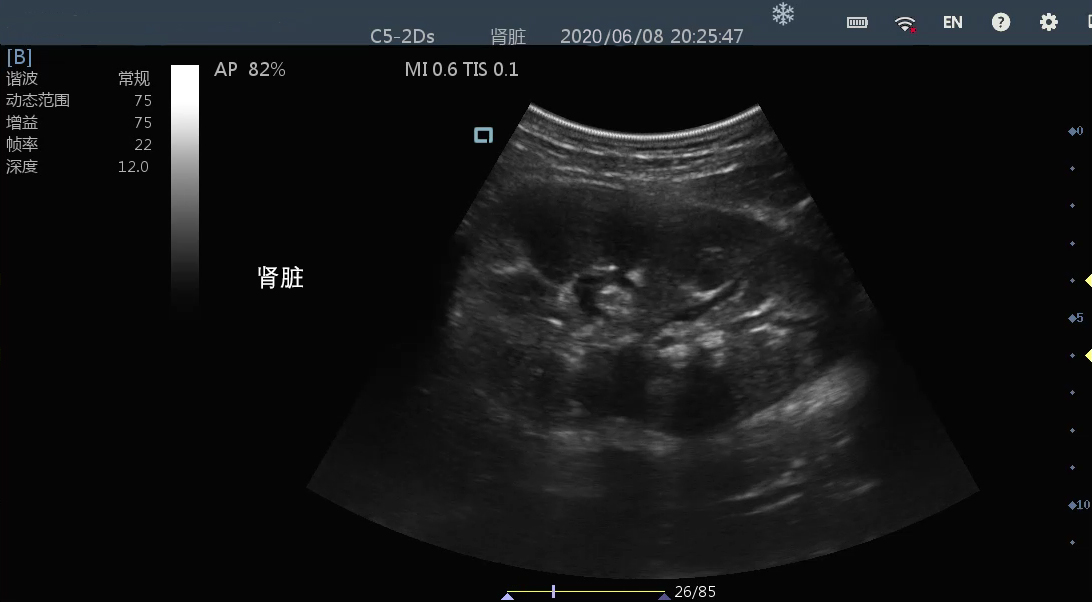

肾脏